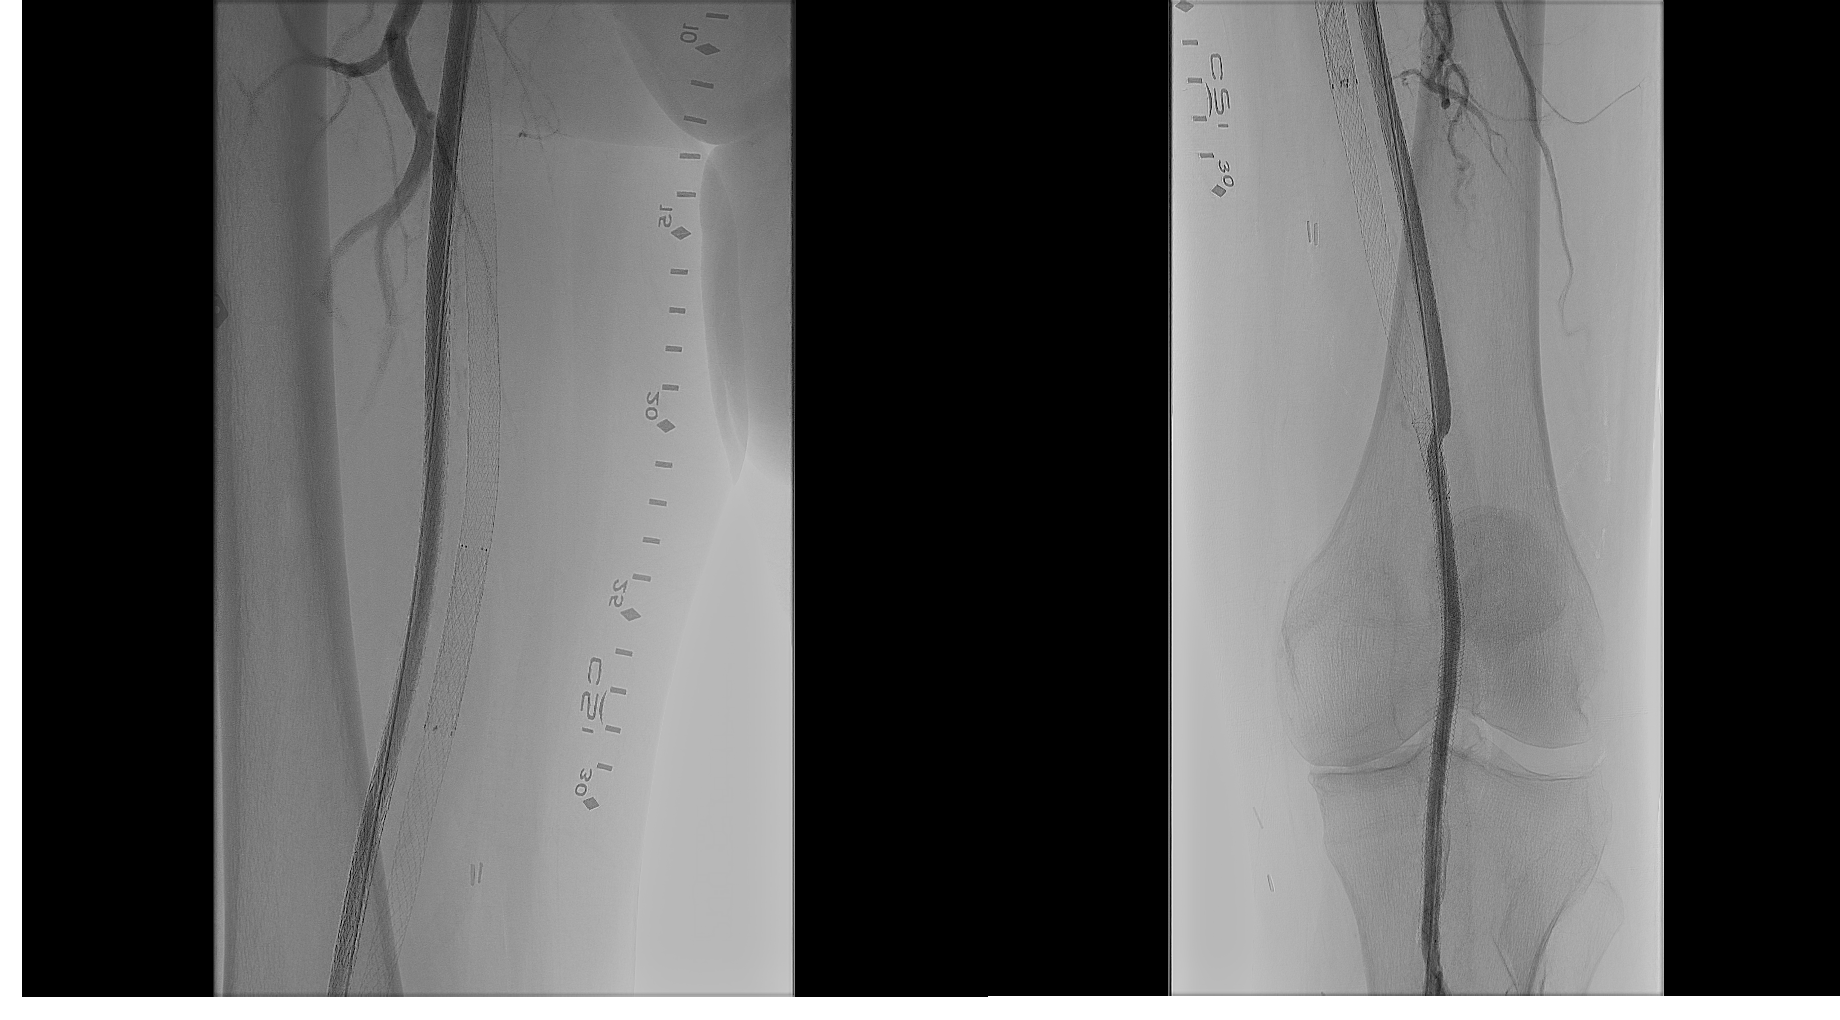

A 76-year-old White man with a medical history of hypertension, tobacco abuse, coronary artery disease, and coronary artery bypass grafting presented with a nonhealing wound of his left lower extremity. He had a previous history of stenting of the left superficial femoral artery (SFA) 8 years prior to presentation. He was noted to have complete occlusion of the left SFA and also abrupt occlusion of the left common and profunda femoral artery (Figure 1). The patient was offered an above-knee amputation, which he refused, and opted for endovascular intervention for revascularization of his entire left lower extremity.

Based on his comorbidities, history of recurrent stenting of the left SFA, and an occlusion of the SFA over 200 cm, he was deemed to be an appropriate candidate for percutaneous transmural arterial bypass (PTAB). However, in order to establish long-term patency, we proceeded to gain posterior tibial artery access to identify a 3-vessel runoff (Figure 2). With this information, using the outline of the stents in left SFA and using a 0.018-in Glidewire Advantage (Terumo) and a 0.018-in Rubicon catheter (Boston Scientific), we were able to obtain access into the left profunda femoral artery (Figure 3). Despite multiple-balloon angioplasty, the recoil within the left common femoral artery (CFA) left little option but to place a 7.0-mm Eluvia stent (Boston Scientific), which was overlapped with the proximal stent in the left SFA (the profunda femoral artery was patent after balloon angioplasty; Figure 4).